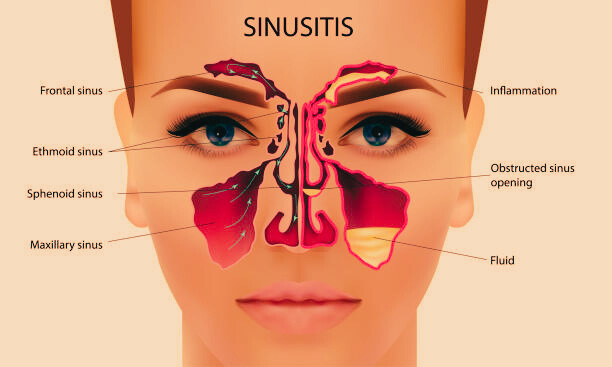

sinusitis